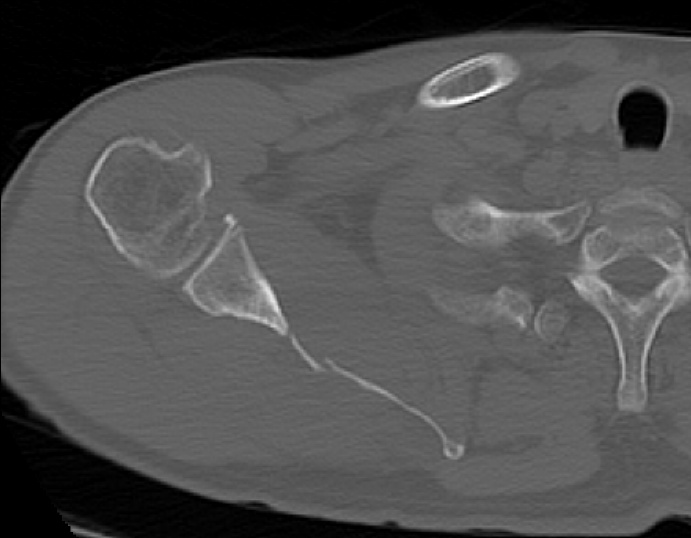

2022.06.07 CT SCAN

- M/50대

- fall down

- X-Ray 검사 상 견갑골 골절의심 됨

- Axial Scan 후 MPR로 Axial, Coronal, Sagittal image Recon 함

- Rib CT 포함하여 검사함.

mildly displaced fracture of body of scapula.